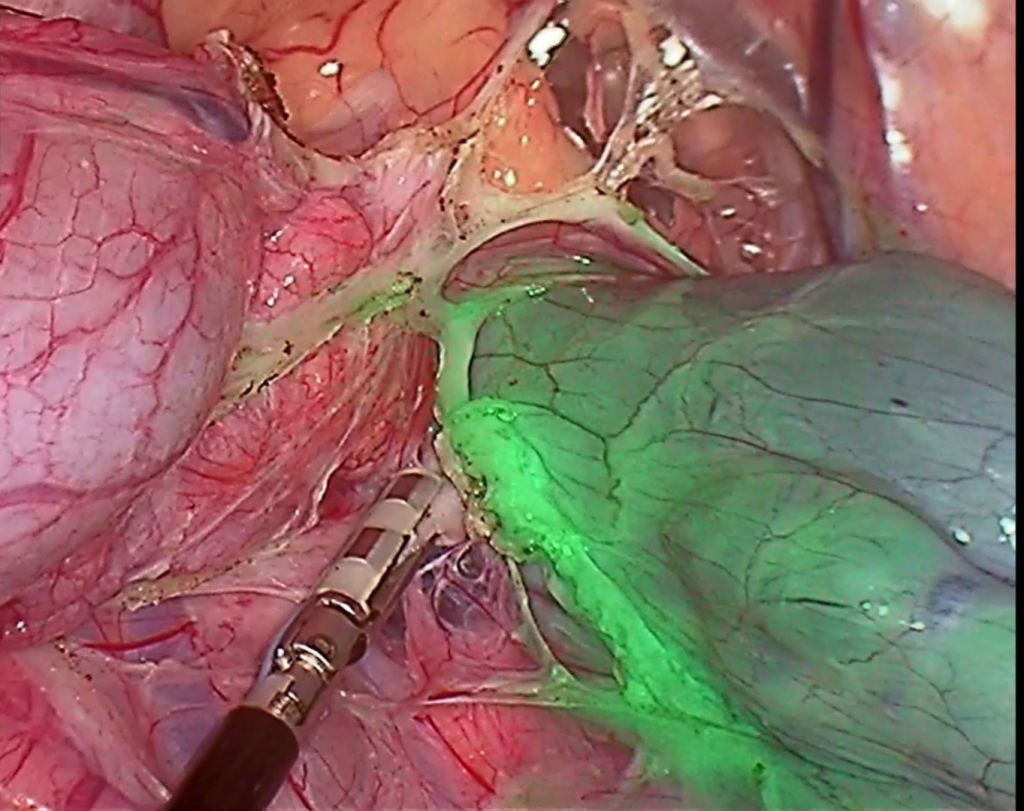

Vision systems

• Laparoscopy